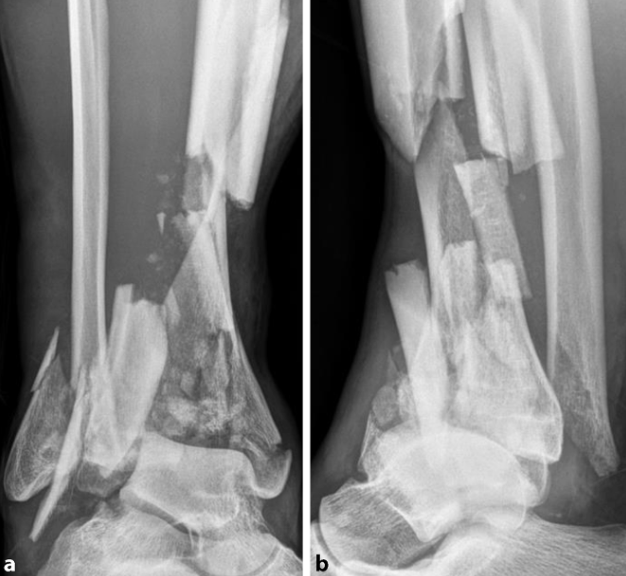

图a、b.术前X线显示Pilon骨折(AO 43-C3 型)。一个较大的后侧关节骨折块(黄色轮廓标注)可简单延伸至骨干区域;c、d. 通过前外侧入路(c,蓝色虚线标注),使用复位钳将后侧关节骨折块(d,黄色轮廓标注)解剖复位到骨干上,并用2枚螺钉固定。通过这一操作,将C型骨折转化为B型骨折。